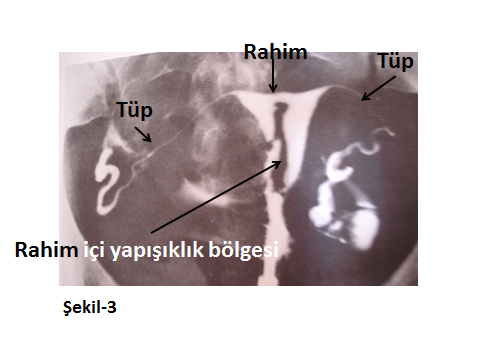

Aşağıda farklı HSG görüntüleri ile konu görsel hale getirilmeye çalışılmıştır.

Şekil-3’teki HSG görüntüsünde ise; rahim içinde sonradan oluşmuş yapışıklıkların varlığı izlenmektedir. Tekrarlayan ya da uygun koşulları ile yapılmamış küretajlar, rahim içini de ilgilendiren geçirilmiş cerrahiler, enfeksiyon sekelleri vb. nedenlerle oluşmuş yapışıklıklar, infertilite ve adet bozuklukları gibi sorunlara neden olurlar. Bunlar, tanıları konulduğunda, operatif histeroskopi ile etkin bir şekilde tedavi edilebilir.